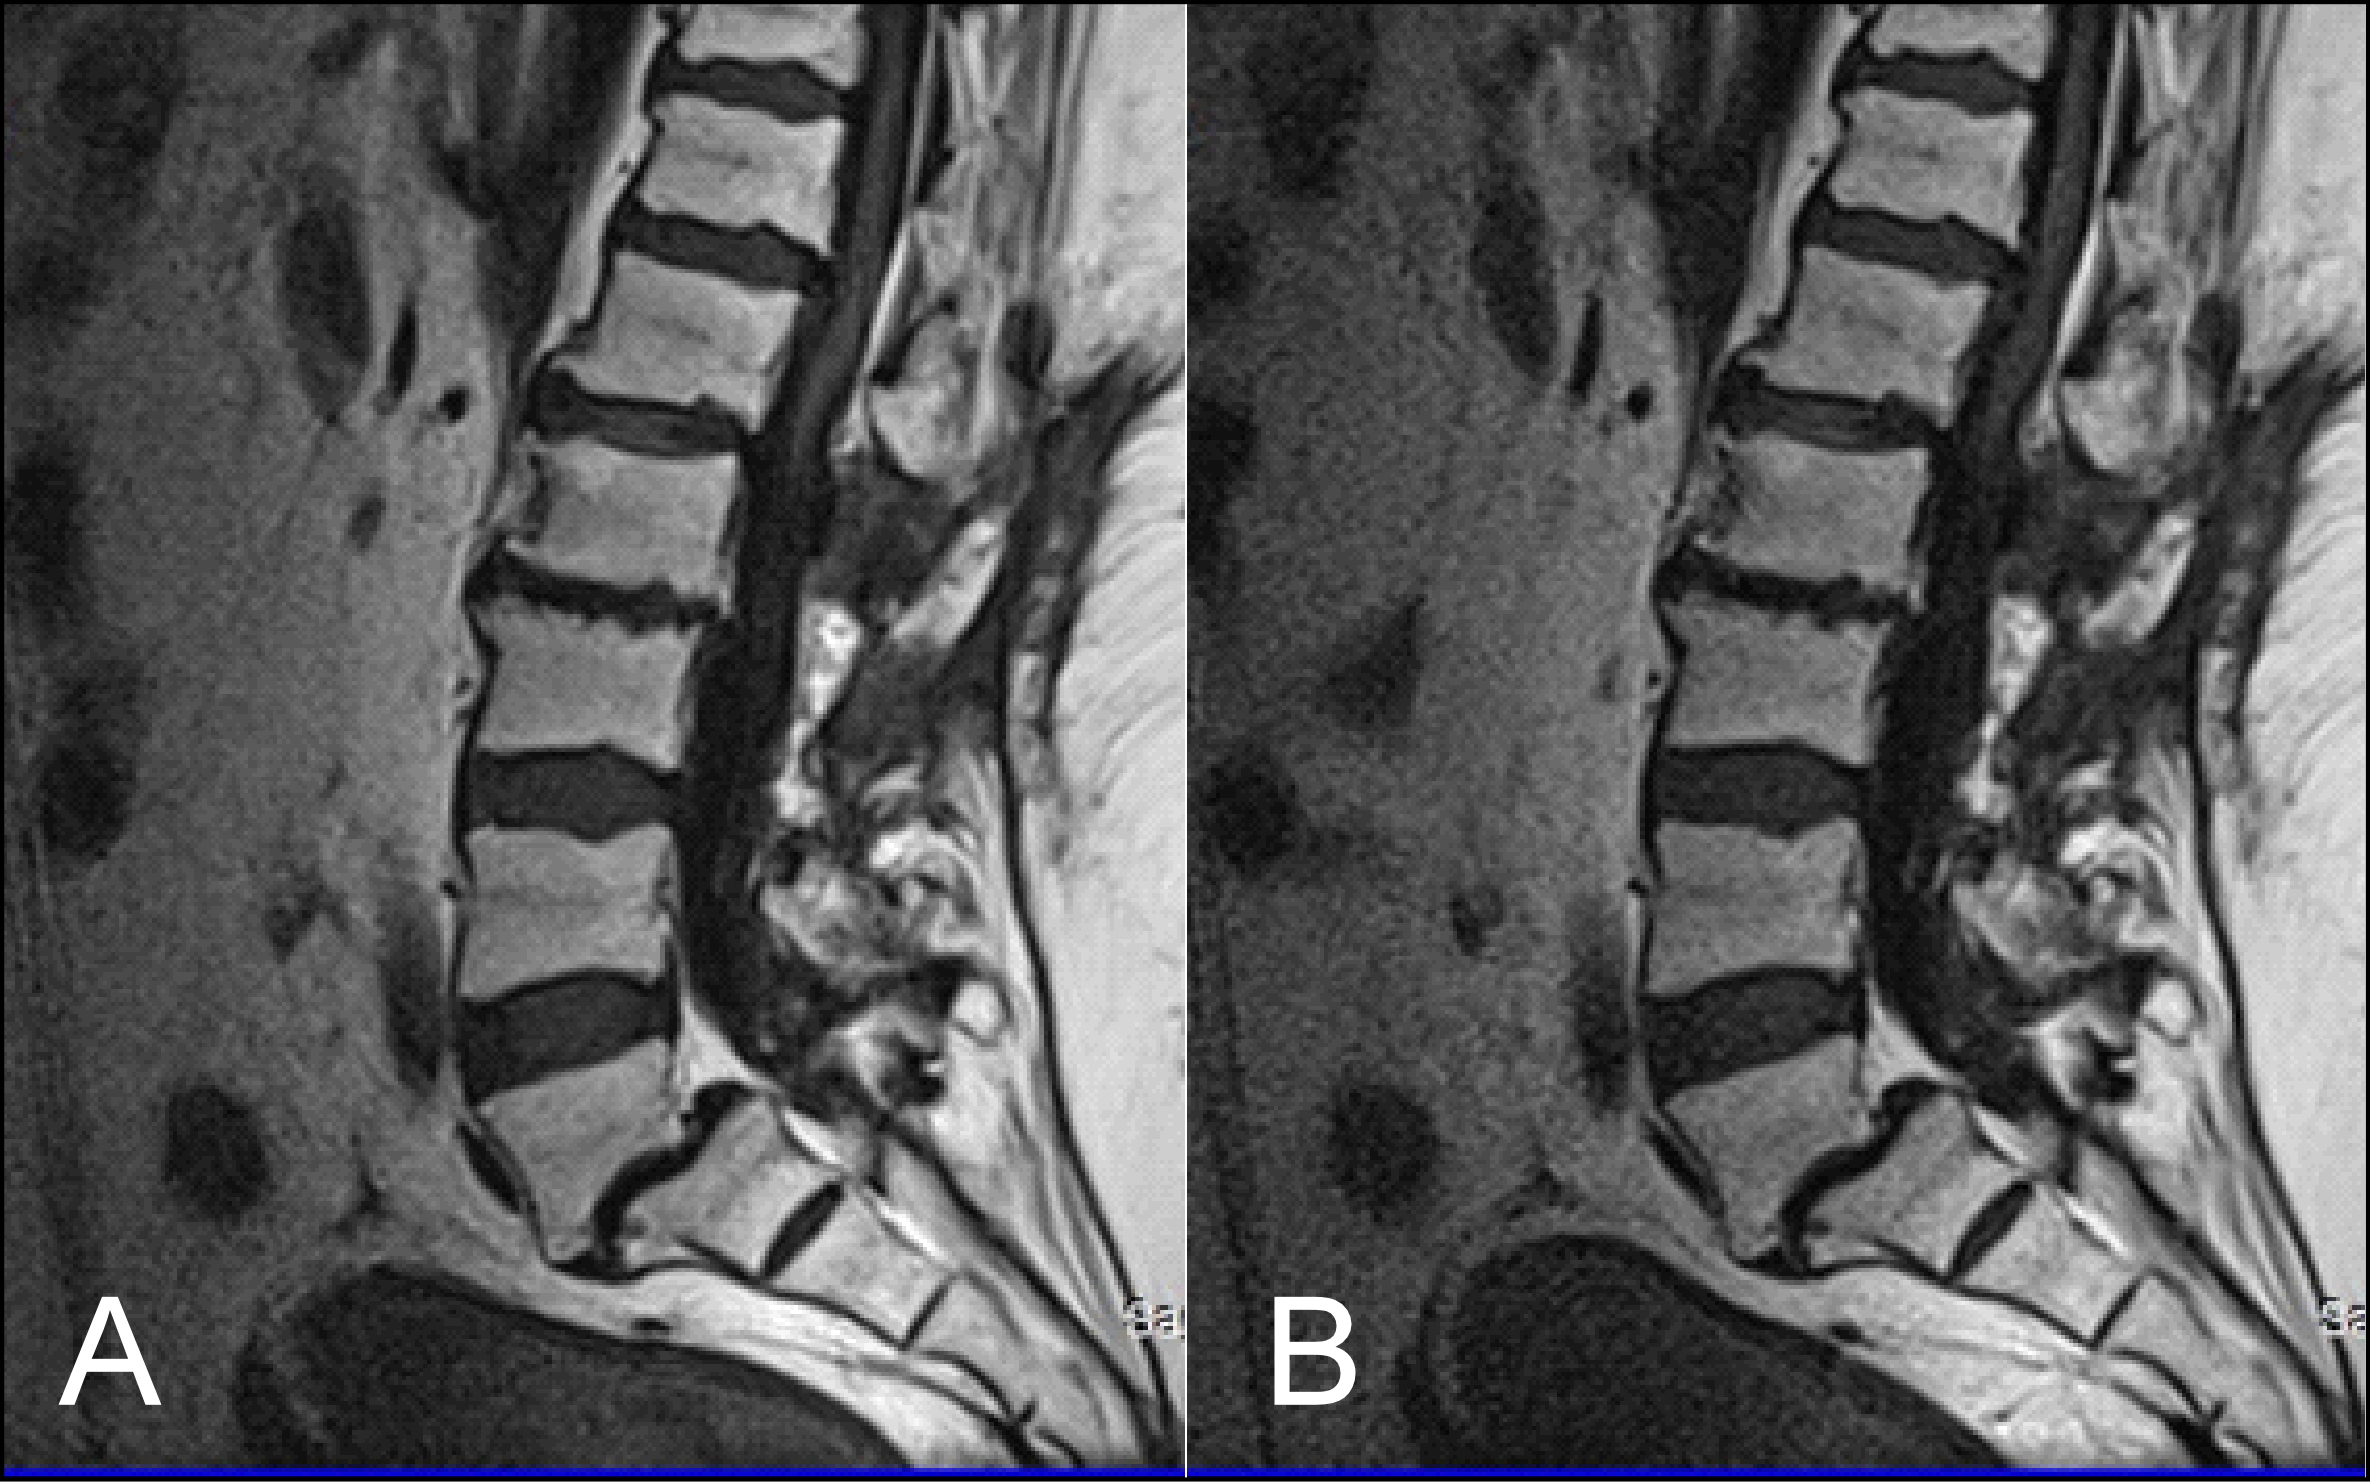

As stated earlier, sagittal T1 weighted images play an integral role in the MR imaging of the L-spine. One of the reasons is that they provide great information about anatomical structures. In order to assess the importance of the BLADE sequence compared to a TSE, both a qualitative and quantitative analysis were performed by evaluating contrast in between anatomical structures and the SNR, CNR and ReCon measurement respectively [18]. Although T1W-TSE is a faster sequence, T1W-FLAIR BLADE scored better in quantitative and qualitative analyses. Pathologies and abnormalities were better visualized in the latter one. Furthermore, in T1W-FLAIR BLADE there was improved image contrast as well as greater depiction of anatomical structures and either degeneration or metastatic lesions. Both the quantitative and qualitative analysis showed that T1W-FLAIR BLADE achieved better results than T1W-TSE. In addition to that, T1W-FLAIR BLADE images without parallel imaging were found to have better quality than the T1W-FLAIR BLADE images with parallel imaging. Although they both eliminated motion artifacts, the images without parallel imaging have better SNR as well as better contrast between tissues (Figure 3). Moreover, a study showed that T1W-FLAIR images can successfully eliminate chemical shift artifacts compared to T1W-TSE due to greater receiver bandwidth [8]. This statement was confirmed by our findings (Figure 4).

T1W-FLAIR BLADE also had higher values in all the relative contrast measurements. T1W-FLAIR BLADE showed better results when comparing CSF with spongy bone, CSF with intervertebral disc and intervertebral disc with spongy bone. These results from the quantitative analysis meant better conspicuity between the following anatomical structures: intervertebral disc-CSF, intervertebral disc-spinal cord, vertebral body-CSF and spinal cord-CSF. Both radiologists found that T1W-FLAIR images achieved better CSF nulling compared to T1W-TSE. It was also found that T1W-FLAIR BLADE was significantly superior to T1W-TSE when reviewing the contrast at the spinal cord and cauda equina interface, demonstrating substantial inter-observer agreement. Due to CSF nulling that is achieved in FLAIR sequences, T1W-FLAIR sequence is a very useful tool to distinguish cysts within the spinal cord, tumors and demyelinating disease. Another study showed that T1W-FLAIR images had also a higher CNR over T1W-TSE images in 16 metastatic lesions in the vertebrae, which helped diagnose the extent of the lesion in the spinal cord. Moreover, the findings of this study are in line with the results of other studies, which show that the T1W-FLAIR sequence could be more beneficial for L-spine imaging than T1W-TSE, due to CSF nulling, higher image contrast and definition of anatomical structures, degeneration, or metastatic lesions (Figure 5) [11]. The results of our study also support the above, i.e., T1W-FLAIR BLADE being superior to T1W-TSE for the aforementioned reasons.